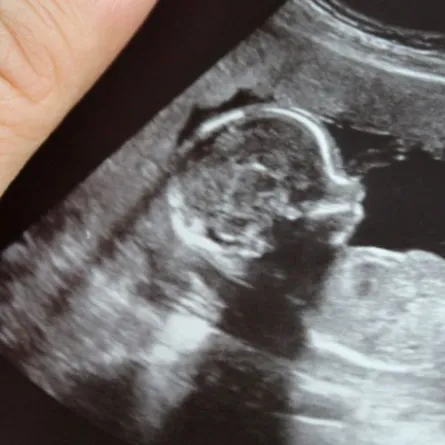

تُعتبر رعاية ما قبل الولادة أمراً بالغ الأهمية لحمل صحي. يمكن أن تساعد فحوصات ما قبل الولادة المنتظمة مع الطبيب في تحديد أي مضاعفات محتملة في وقت مبكر ومنعها من أن تصبح أكثر خطورة. تشمل رعاية ما قبل الولادة مراقبة نمو الطفل.